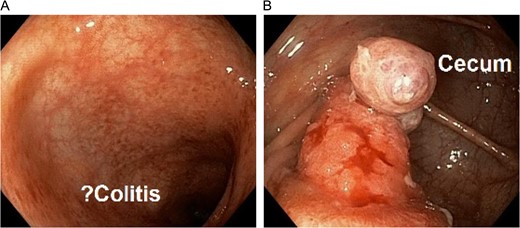

CT with oral and IV contrast demonstrated cecal thickening without visualization of the appendix (Fig. 1). A colonoscopy was performed, which showed mild diffuse erythema and edema in the last 40 cm of the ascending colon as well as a mass within the lumen of the cecum (Fig. 2). Biopsies of the colon demonstrated chronic active colitis and ulceration of the cecal mass, suggestive of mild UC (Fig. 3, bottom right and left). No granulomata were present, and there was no evidence of dysplasia. The decision was made for operative management due to continuation of her symptoms and need for definitive diagnosis.

Colonoscopy demonstrating questionable active colitis in the ascending colon (left) and a mass in the cecum (right).